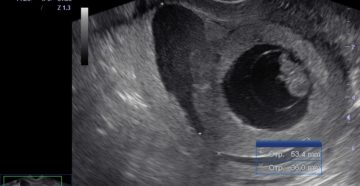

Что такое ретрохориальная гематома, и как её лечат? Ретрохориальная гематома – нередкий диагноз, о котором…